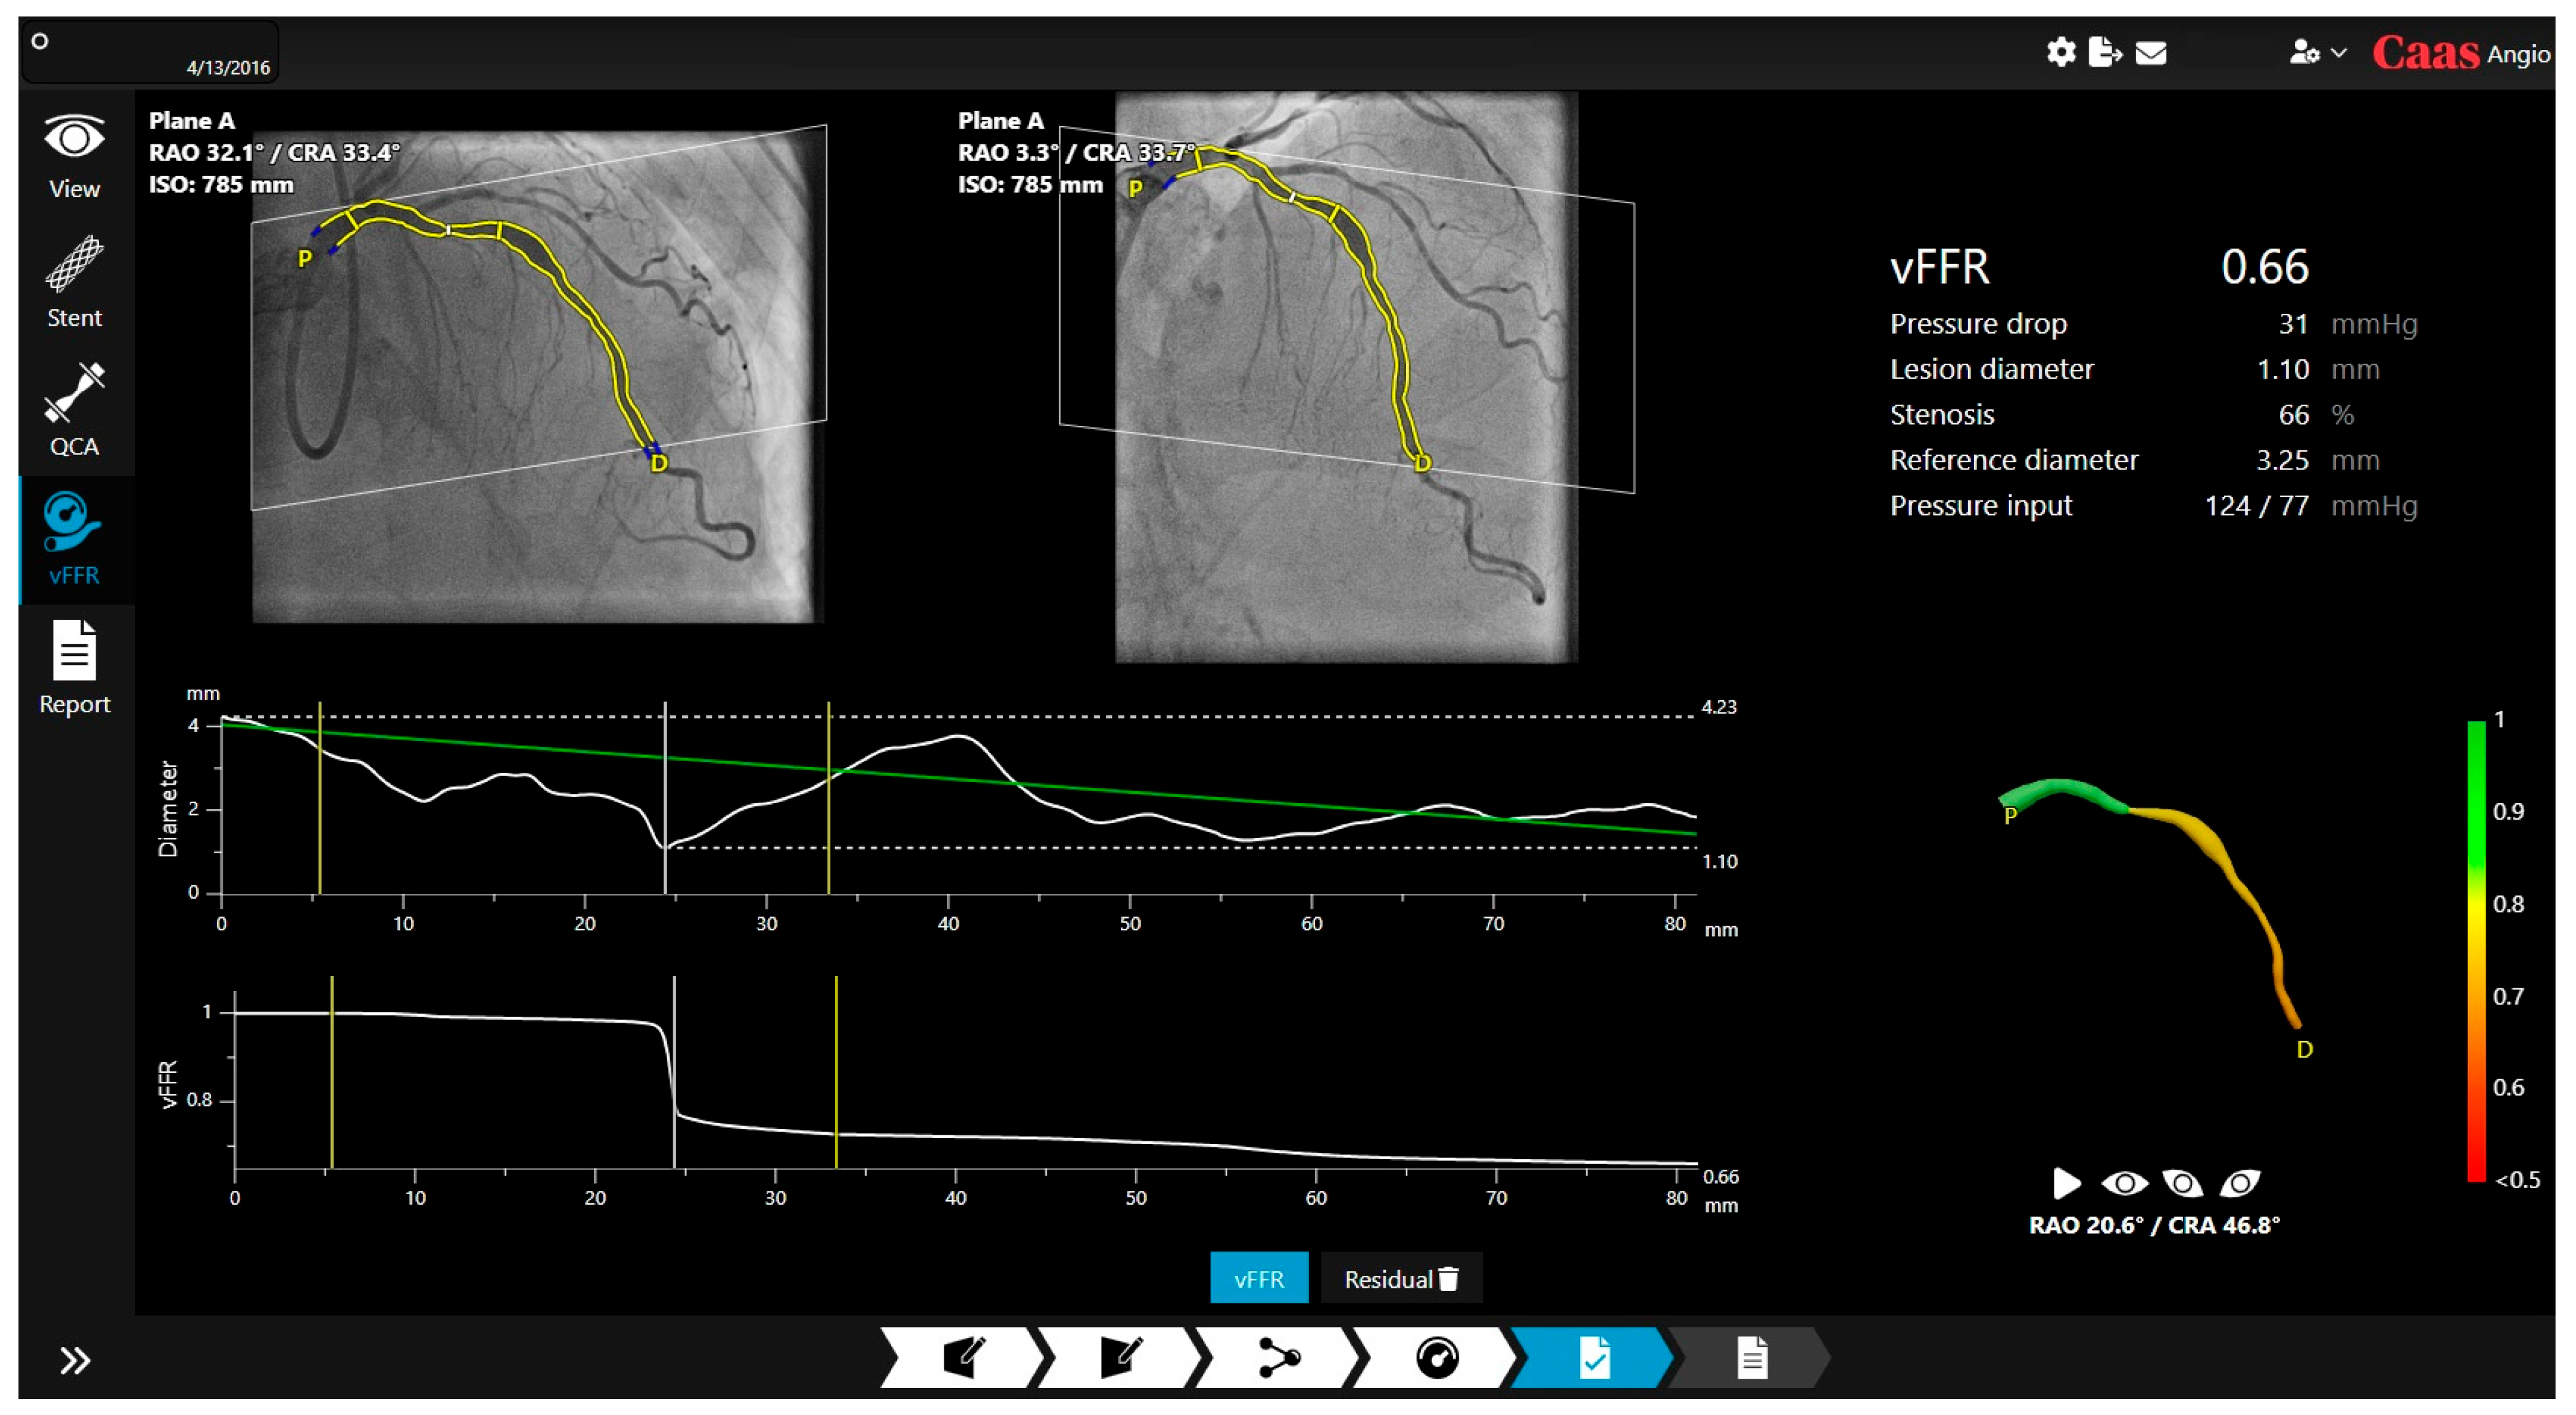

vFFR was developed on the principle of the Navier–Stokes equations, which are fundamental partial differential equations to describe the motion of fluids [6] (Figure 3). This software requires two angiographic views at least 25 degrees apart and supports single vessel analysis [17]. It can generate a virtual FFR pullback and provide a reference diameter for sizing; with a recent update, residual vFFR estimates post-treatment physiology to predict procedural effectiveness [18]. The system also features co-registration of residual vFFR which does not have FDA clearance and is not currently available for clinical use in the United States.

Figure 3. Example of vFFR output interface (reprinted with permission from Ref. [19]. Copyright 2025 Pie Medical Imaging).